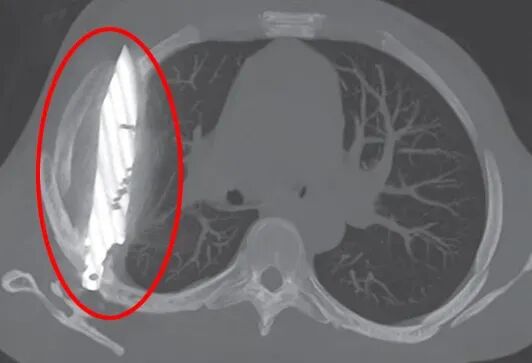

胸部X光检查结果让所有医生都大吃一惊——一把巨大的刀片竟然完整地插在患者胸腔内。影像显示,这把刀从右肩胛骨刺入,奇迹般地避开了所有重要器官。

外科医生在手术中小心翼翼地取出了刀片,同时清除了由坏死组织引起的脓液。患者在重症监护室观察了24小时后,被转至普通病房继续治疗10天。